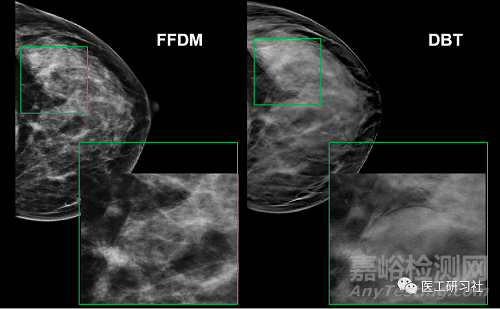

常規(guī)乳腺X射線是為平片成像, 具有乳腺組織的堆疊效應(yīng),致使其病灶檢出率降低, 易造成誤診、漏診等。數(shù)字乳腺斷層攝影(Digital Breast Tomography, DBT)技術(shù)以傳統(tǒng)的數(shù)字乳腺攝影為基礎(chǔ),在有限角度內(nèi)對乳腺組織進(jìn)行數(shù)次曝光,不僅可以產(chǎn)生二維數(shù)字化乳腺圖像, 還可以重建乳腺的斷層圖像,能夠更加清晰的看到乳腺組織和病灶結(jié)構(gòu)。

DBT較好地解決了乳腺纖維腺體組織重疊的問題,較大程度上避免了因重疊乳腺組織掩蓋的乳腺癌變組織導(dǎo)致的漏診,從而提高了乳腺癌檢出的敏感度,進(jìn)而降低假陽性率。

與FFDM相比,DBT產(chǎn)生的二維合成乳房X線圖在不增加輻射劑量的情況下,對乳腺癌的診斷效率有了明顯的提高,尤其是在致密型的乳腺中具有更高的應(yīng)用價(jià)值。根據(jù)2018年發(fā)布在《柳葉刀·腫瘤學(xué)》的一篇文獻(xiàn),對于乳腺癌篩查,DBT的特異性和靈敏性分別是97.2%和81.1%,而傳統(tǒng)方法的特異性也有98.1%,但靈敏性卻只有60.4%。

根據(jù)2022年發(fā)表在《Radiology》的最新研究,在致密性乳腺中,數(shù)字乳腺斷層攝影(DBT)聯(lián)合二維合成乳腺X線圖像(synthesized mammography,SM)對于浸潤性乳腺癌的檢出率是單獨(dú)數(shù)字乳腺X線攝影(Digital Mmmography,DM)的3倍。

DBT在致密乳腺診斷具有優(yōu)勢(來自網(wǎng)絡(luò))